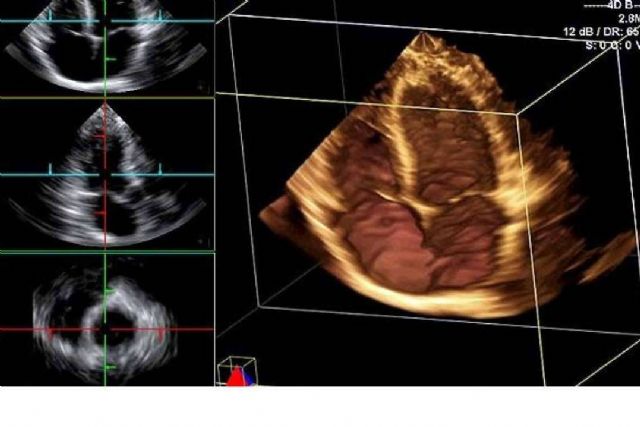

La línea de ecógrafos de SCPmedical se caracteriza por su portabilidad, conectividad y facilidad de manejo. Los modelos inalámbricos permiten trabajar en movimiento, sin cables, optimizando el espacio y mejorando la higiene en entornos sensibles. A su vez, los dispositivos portátiles ofrecen la posibilidad de realizar exámenes de imagen directamente junto al paciente, tanto en hospitales como en consultas externas, residencias o unidades móviles.